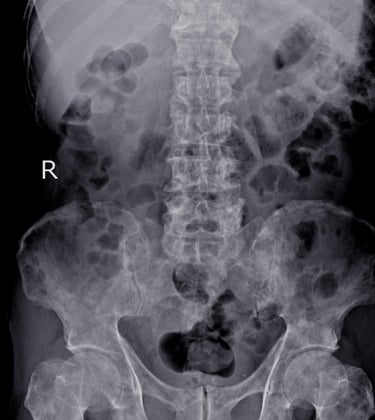

RADIOLOGÍA

Embárquese en este viaje educativo y conquiste el futuro de la radiología, donde el conocimiento avanzado se combina con la práctica , preparándolo para sobresalir en una carrera llena de oportunidades y logros.

El área de radiología, con docentes altamente calificados para brindarte lo mejor en esta nueva era de la inteligencia artificial y cómo cambia todo lo que sabemos del área, además de tener contenido de radiología, también habrá informática. x contenido de radiología para mantenernos actualizados en todo lo relacionado con PACS, HIS, LIS, RIS.